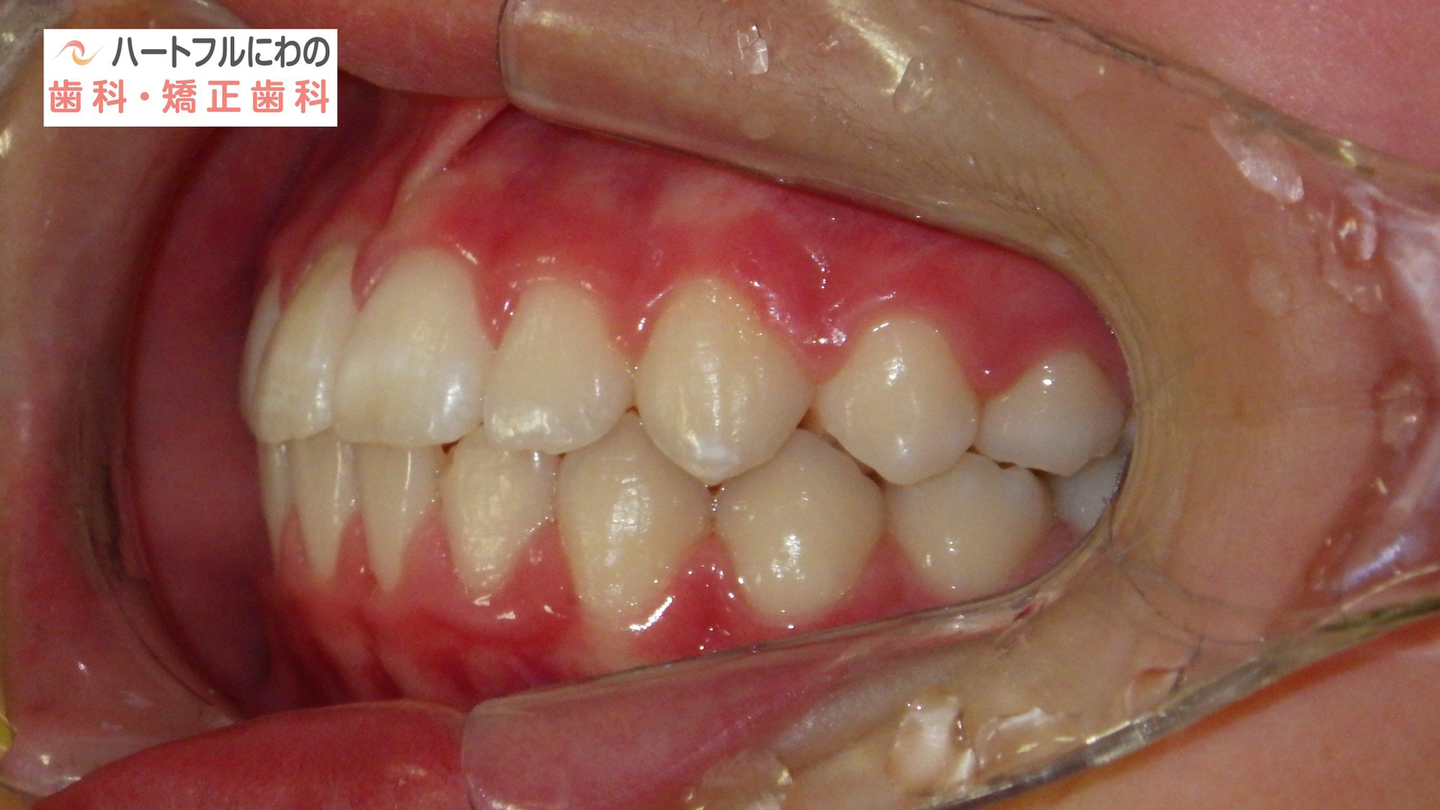

奥歯と前歯の前後的位置関係は大きく改善し、正常になりました。